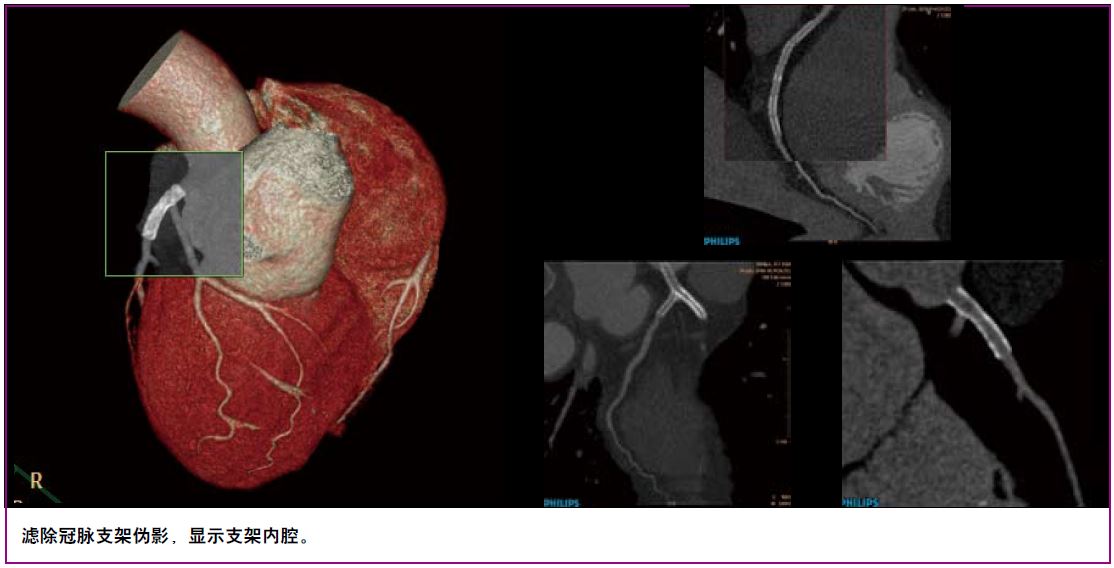

显微成像——动态四焦点及纳米探测器实现4800采样/0.27秒最高采样率,丰富信息成就1024x1024超高分辨成像技术,4倍信息量提升令微小病灶诊断不再困惑。同时高效的祛金属伪影O-Mar功能防止漏诊情况。

O-Mar可以有效祛除金属伪影,保证有效的还原原有的图像